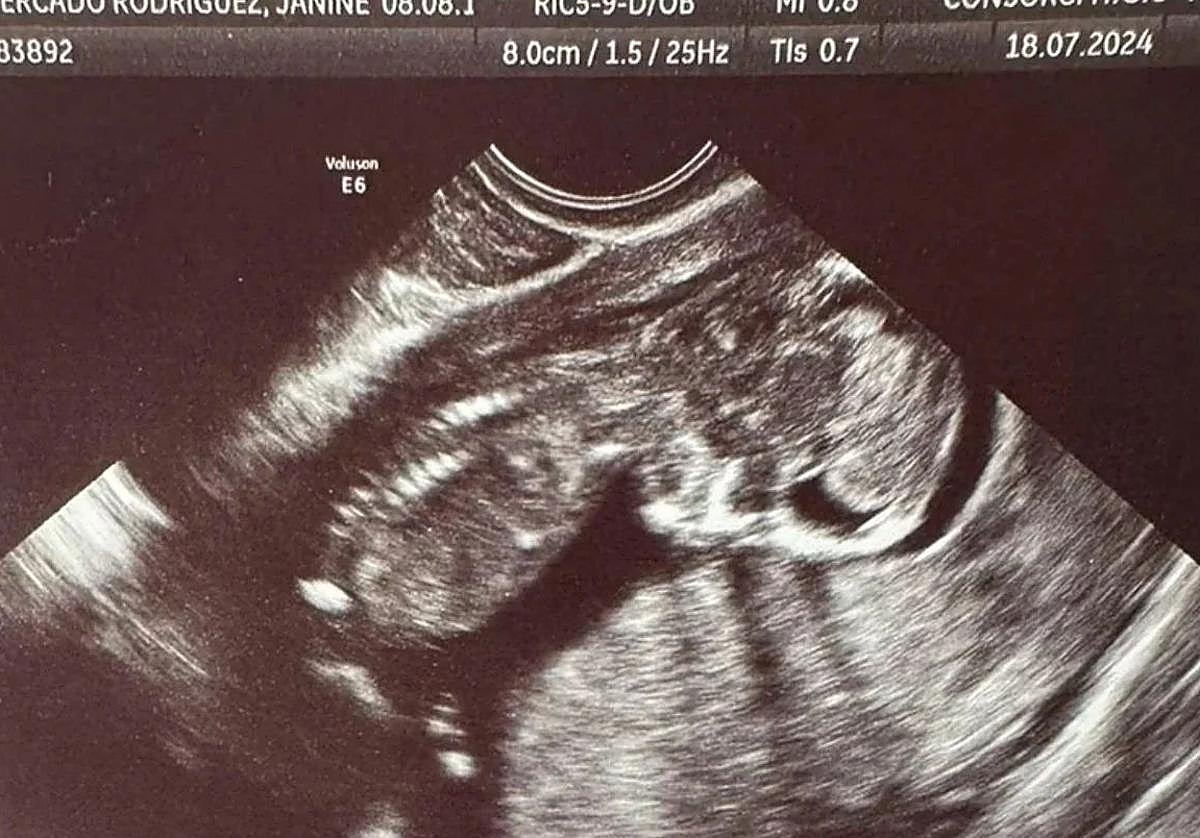

Ecografía de la pequeña Escarlett facilitada por su abuela. L. P.

«Janine iba a ser madre soltera. Su primera hija era su ilusión y trabajaba duro por ella al volante de un camión. Ahora he perdido a las dos y sólo pido justicia». Lo decía la madre de Janine Mercado Rodríguez. La mamá de Escarlett, arrastrada por las aguas aquel terrible 29 de octubre.